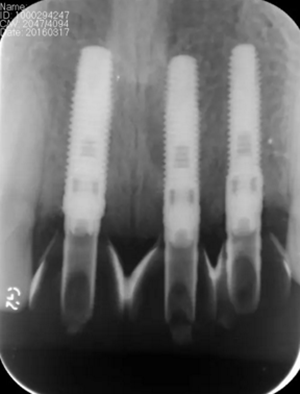

圖3 術(shù)前CBCT

圖13 術(shù)后即刻根尖片

圖17 術(shù)后6個月根尖片

圖24 最終修復(fù)后即刻根尖片